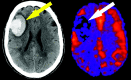

Encephalomalacia. Axial T2-weighted image shows high signal intensity in the frontal lobes representing the remote bilateral anterior cerebral artery (ACA) territory infarcts (yellow arrows). ASL CBF map reveals corresponding focal decrease in flow in the ACA territories (white arrows).

Fig 4.